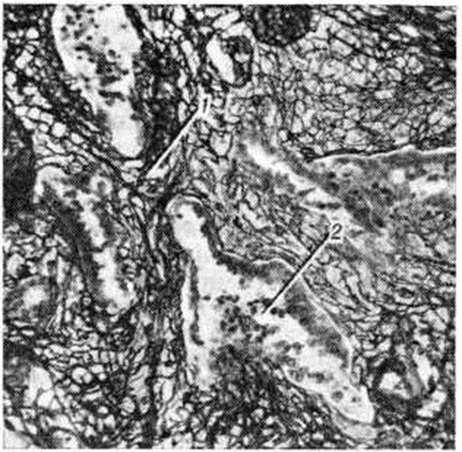

Классификация Вотчала (1962) учитывала этиологию Пневмосклероз с указанием инфекционных и неинфекционных форм, среди которых впервые упоминались химиотоксический, лекарственный, лучевой Пневмосклероз; патогенез с указанием воспалительного, аллергического, экссудативно-дистрофического, смешанного Пневмосклероз; распространённость с выделением ограниченного, рассеянного, многоочагового, диффузного и смешанного Пневмосклероз; функциональные расстройства без выраженного нарушения дыхания, с нарушением бронхиальной проходимости, с ригидностью лёгкого (фиброз), с нарушением диффузии газов и с нарушениями смешанного типа, с сердечной недостаточностью и без неё; активность процесса — стадии обострения и ремиссии; характер течения — прогрессирующий и непрогрессирующий Пневмосклероз В данной классификации отсутствовали формы Пневмосклероз, развивающиеся вследствие пороков развития лёгких, ферментопатий, дистрофий, не был выделен специфический Пневмосклероз, в частности метатуберкулёзный, однако в целом принцип классификации сохранил своё значение и нашёл отражение в современной классификации. Классификация. По этиологии Пневмосклероз делят на инфекционный — специфический (метатуберкулёзный, сифилитический, микотический, паразитарный), неспецифический, в том числе после аспирации инородного тела, и посттравматический; токсический; пневмокониотический; диспластический (вследствие пороков развития лёгкого или врождённых ферментопатий); дистрофический (вследствие лучевого пневмонита, реактивный Пневмосклероз при амилоидозе, микролитиазе, оссификации); аллергический — экзогенный (лекарственный, от вдыхания спор грибов) и эндогенный при фиброзирующих альвеолитах неясной этиологии (синдромы Хаммена — Рича, Гудпасчера, при идиопатическом лёгочном гемосидерозе, при десквамативной и гигантоклеточной интерстициальной пневмонии, коллагеновых болезнях) либо при аллергических гранулематозах (эозинофильной затянувшейся пневмонии, гранулематозе Вегенера, саркоидозе Бека и другие); кардиоваскулярный Пневмосклероз (при приобретённых пороках сердца, врождённых пороках сердечно-сосудистой системы, сопровождающихся гипертензией малого круга кровообращения, при пролонгированных тромбозах и эмболиях малого круга кровообращения). Патогенетически выделяют воспалительный Пневмосклероз (бронхогенный, бронхоэктатический, бронхиолярный, или «сотовое лёгкое», постпневмонический, плеврогенный); ателектатический Пневмосклероз, или фиброателектаз (при синдроме средней доли, инородных телах лёгких, иногда при бронхогенных опухолях); лимфогенный Пневмосклероз, обусловленный лимфоплеторой лёгочного или кардиоваскулярного происхождения; иммунный при ограниченных и диффузных альвеолитах. По патоморфологическим признакам различают: диффузный Пневмосклероз (сетчатый лимфогенный, диффузный альвеолярный, так называемый пневмофиброз, а также миофиброз бронхиол и мелких сосудов); локальный Пневмосклероз (воспалительный, фиброателектатический, диспластический, аллергический — гранулематозный). С учётом нарушения функции лёгких Пневмосклероз может протекать без нарушения дыхания, с нарушением вентиляции по обструктивному типу, с нарушением вентиляции по рестриктивному типу, с гипертензией в малом круге кровообращения или без неё. Кроме того, Пневмосклероз бывает прогрессирующим и непрогрессирующим. Этиология. Наибольшее значение в развитии Пневмосклероз имеет инфекция. Бактерии (стрептококки, стафилококки), некоторые грибки, возбудители паразитарных инфекций (амёбы, токсоплазмы, эхинококки), вызывая нагноение и некроз лёгочной ткани, ведут к развитию бронхоэктазов и пневмоциррозу. Особое место среди инфекционные факторов, вызывающих Пневмосклероз, занимает туберкулёз. При некоторых вторичных формах туберкулёза (фиброзно-кавернозный, цирротический) метатуберкулёзный Пневмосклероз носит локальный деформирующий характер, при гематогенно-генерализованном туберкулёзе — диффузный лимфогенный. Большую роль в развитии метатуберкулёзного Пневмосклероз играет малоэффективная терапия, а также присоединение неспецифического бронхита. Тяжёлый деформирующий Пневмосклероз в виде «дольчатого лёгкого» может развиться при третичном сифилисе. Вирусные инфекции, не осложнённые бактериальной инфекцией, редко приводят к Пневмосклероз, и если последний развивается, например, при орнитозе, то носит характер фиброзирующего альвеолита. Инфекционный Пневмосклероз возникает также при аспирации инородных тел, носит при этом характер опухолевидного образования и вызывает ателектатическое сморщивание значительных отделов лёгких. Близок к инфекционному посттравматический Пневмосклероз, так как в условиях травмы нарушается очистительная функция бронхов, в них активизируются возбудители инфекции, в том числе условно-патогенная флора, гематомы нагнаиваются с развитием абсцессов, что приводит к циррозу лёгких. К. Г. Никулин (1972), наиболее подробно описавший посттравматический Пневмосклероз, различает следующие его формы: ранний и поздний, ограниченный и диффузный, плевральный и лёгочный. Наиболее грубый Пневмосклероз возникает при наличии массивного гемоторакса и пневмоторакса, способствующих ателектазам. Особенно быстро Пневмосклероз развивается при слепых осколочных ранениях, чему способствуют кровоизлияния, аспирация крови с последующей её организацией. При «шоковом лёгком» (смотри полный свод знаний: Лёгкие), наблюдаемом при травме, развивается альвеолярный пневмофиброз. Токсический Пневмосклероз, преимущественно диффузный, в военное время может быть обусловлен действием боевых отравляющих веществ, в мирное — промышленными газами, например, двуокисью азота, а также кислородом при неправильном его применении в процессе лечения, под воздействием высоких концентраций озона и продуктов сгорания пластмасс, повреждающих сурфактант (смотри полный свод знаний). Играет роль не только превышение допустимых концентраций промышленных газов во вдыхаемом воздухе, но и индивидуальная чувствительность к ним. Опасно сочетание токсических газов с туманами (так называемый смог). Пневмокониотический Пневмосклероз возникает в результате запыления воздуха промышленными, минеральными и растительными веществами (смотри полный свод знаний: Пневмокониозы). Наибольшую роль в развитии соединительной ткани в лёгком играют двуокись кремния и бериллий. При бериллиозе (смотри полный свод знаний: Бериллий) особое значение придаётся индивидуальной чувствительности. Диспластический Пневмосклероз обусловлен аномалиями лёгких, чаще всего кистозной гипоплазией (смотри полный свод знаний: Лёгкие), или ферментопатиями — муковисцидозом (смотри полный свод знаний), дефицитом о-антитрипсина, способствующим развитию эмфиземы. При муковисцидозе, помимо нарушения проходимости бронхов вследствие наличия густого секрета, играет роль наследственная аномалия гликозоаминогликанов в фибробластах, а следовательно, нарушение обмена в соединительной ткани лёгких. Дистрофический Пневмосклероз развивается в виде очагов разрастания соединительной ткани, её обызвествления или оссификации, локализующихся в окружности масс амилоида (смотри полный свод знаний: Амилоидоз). Дистрофический характер носит Пневмосклероз, развивающийся при лучевом пневмоните (смотри полный свод знаний: Пневмония), при котором непосредственное лучевое повреждение вызывает некроз, дистрофию альвеолоцитов, причём развитие лучевого Пневмосклероз зависит не столько от дозы ионизирующего излучения, сколько от индивидуальной чувствительности. Соединительная ткань развивается в эксперименте, по данным Бублитца (G. Bublitz, 1973), спустя 8 недель после действия ионизирующего излучения в основном по ходу альвеол. Более грубые рубцы возникают при присоединении тромбоза. Аллергический фиброзирующий альвеолит, в результате которого развивается диффузный альвеолярный Пневмосклероз (пневмофиброз), может носить экзогенный и эндогенный характер. К экзогенным относят фиброзирующий альвеолит, возникающий при приёме лекарственных средств (гексаметония, блеомицина, метотрексата, препаратов нитрофуранового ряда, сульфаниламидов, циклофосфамида). Экзогенный характер носит также аллергическая реакция лёгких на вдыхание пыли прелого сена («лёгкие фермера»), завершающим этапом которой может быть диффузный альвеолярный Пневмосклероз (смотри полный свод знаний: Экзогенные аллергические альвеолиты). Природа эндогенного фиброзирующего альвеолита неизвестна; он развивается при коллагеновых болезнях, синдромах Хаммена — Рича (смотри полный свод знаний: Хаммена — Рича синдром), Гудпасчера (смотри полный свод знаний: Лёгкие), Картагенера (смотри полный свод знаний: Лёгкие), идиопатическом гемосидерозе лёгких (смотри полный свод знаний), интерстициальной пневмонии (смотри полный свод знаний), а также аллергическом гранулематозе Вегенера (смотри полный свод знаний: Вегенера гранулематоз), саркоиде Бека (смотри полный свод знаний: Саркоидоз). К эндогенному идиопатическому фиброзирующему альвеолиту относят также наследственный идиопатический фиброз лёгких близнецов, описанный Пибоди (J. W. Peabody, 1950). Кардиоваскулярный Пневмосклероз возникает при митральном пороке сердца (порок левого предсердно-желудочкового клапана) любой этиологии и врождённых пороках сердца с гипертензией малого круга кровообращения, пролонгированных тромбозах и эмболиях лёгких, ангиитах, сопровождающихся нарушением оттока по лимфатических, сосудам. Патогенез. Пневмосклероз может возникать в результате различных патологический процессов. При инфекциях, пневмокониозах, травмах, воздействии токсических веществ наибольшее значение в развитии Пневмосклероз имеет воспаление (смотри полный свод знаний). Среди Пневмосклероз воспалительного происхождения различают метапневмонический, бронхогенный, бронхоэктатический, бронхиолярный и плеврогенный. В основе гистогенеза воспалительного Пневмосклероз лежат карнификация (смотри полный свод знаний), созревание грануляционной ткани, если имелось нагноение или некрозы, фиброз очагов интерстициального воспаления межальвеолярных перегородок. Воспалительная инфильтрация и склероз стенок бронхиол ведут к развитию так называемый сотового лёгкого с деструкцией межальвеолярных перегородок и формированием множественных полостей. Наибольшее значение среди Пневмосклероз воспалительного происхождения имеет бронхогенный Пневмосклероз, поскольку бронхи являются открытой средой для инфекции. Однако процесс не носит изолированного перибронхиального характера, а быстро становится периваскулярным в связи с обилием коллатералей между лимфатических, сосудами, оплетающими бронхи и кровеносные сосуды лёгких. Нарушение лимфогенного и бронхогенного дренирования вследствие бронхита (смотри полный свод знаний) или бронхиальной гиперсекреции способствует переходу воспаления на лёгочную ткань. Аналогичная ситуация возникает при кортикоплеврите (смотри полный свод знаний: Плеврит), особенно если присоединяются эмпиема или пневмогемоторакс, затрудняющие лимфообращение в лёгком вследствие ограничения его подвижности. Однако плеврогенный Пневмосклероз в отличие от бронхогенного имеет более локальный характер и захватывает поверхностные слои лёгкого вследствие карнификации или пневмонии. Бронхоэктатический Пневмосклероз обусловлен перифокальным воспалением интерстиция межальвеолярных перегородок, ателектазами, развитием грануляционной ткани. Цирротической деформации подвергаются сосуды, особенно сосуды корня лёгкого, что может привести к аневризматическому расширению одних и сдавливанию других сосудов. Деформация сосудов способствует шунтированию крови, нарушению насыщения крови кислородом, усилению кровенаполнения бронхиальных вен, что служит причиной их расширения, кровотечений и бронхиальной гиперсекреции. Ателектатический Пневмосклероз, или фиброателектаз, возникает при большинстве вышеупомянутых этиологического форм и имеет в своей основе нарушение преимущественно лимфообращения. Лимфоплетора, развиваясь в малоподвижном участке лёгкого (ателектазе), сопровождается истечением лимфы, пропитыванием сближенных между собой фиброзных прослоек стромы лёгкого белками и их метаболитами, что вместе с возникающей при этом гипоксией способствует пролиферации фибробластов и, следовательно, фибриллогенезу. Однако при асептически протекающем ателектазе Пневмосклероз, как правило, выражен незначительно. В случае присоединения воспаления он существенно усиливается, приобретая форму так называемый фиброателектаза. Фиброателектаз проявляется наиболее интенсивно при так называемый синдроме средней доли — неспецифическом процессе, обусловленном сдавлением средне-долевого бронха, характеризующегося большой длиной и узким просветом. Лимфогенный Пневмосклероз также имеет в основе лимфоплетору, но развивается без сближения тканевых элементов лёгкого, то есть без ателектаза, и только по ходу крупных лимфатических, коллекторов в фиброзных прослойках лёгкого. В той или иной степени этот механизм включается при всех этиологического формах Пневмосклероз, в том числе при Пневмосклероз кардиоваскулярного происхождения. В этом случае он часто бывает единственным проявлением Пневмосклероз, за исключением последних стадий «бурой индурации», когда присоединяется склероз межальвеолярных перегородок (смотри полный свод знаний: Бурое уплотнение лёгких). Пневмосклероз иммунного происхождения развивается при большинстве форм фиброзирующего альвеолита и гранулематоза лёгкого. В его основе лежит отложение иммунных комплексов и скопление иммунокомпетентных клеток (лимфоцитов, плазмоцитов, а также эозинофилов) по ходу базальной мембраны межальвеолярных перегородок. Количество клеток варьирует в зависимости от типа аллергической реакции. Процесс чаще имеет системный двусторонний характер. Патологическая анатомия. Морфологически картина Пневмосклероз определяется распространённостью патологический процесса, особенностями патогенеза и в меньшей степени этиологией, значение которой наиболее выражено при инфекционных формах Пневмосклероз Выделяют диффузные и локальные формы Пневмосклероз. Среди диффузных форм Пневмосклероз различают сетчатый лимфогенный (перибронхиальный, периваскулярный, перилобулярный), диффузный альвеолярный Пневмосклероз, или пневмофиброз, миофиброз гладких мышц бронхиол и мелких сосудов (артериокапиллярный Пневмосклероз). Указанные формы Пневмосклероз определяются вовлечением в патологический процесс фиброзной, ретикулярной и гладкомышечной стромы лёгкого. Сетчатый лимфогенный Пневмосклероз имеет крупноячеистый характер, развивается в пределах фиброзной стромы лёгкого, которая окутывает сосуды и бронхи первых порядков ветвления, иммобилизируя их при дыхательных экскурсиях лёгких. Она же разделяет анатомические сегменты лёгкого и сливается с висцеральной плеврой; в фиброзной строме проходят вена и лимфатических, сосуды, но нет капилляров. Сетчатый лимфогенный Пневмосклероз не имеет специфических морфологический признаков, встречается при всех этиологического формах Пневмосклероз, в том числе при гематогенно-диссеминированном туберкулёзе, кардиоваскулярной патологии. Ограниченный плеврогенный Пневмосклероз характеризуется обширными швартами и диффузным сетчатым, в основном периваскулярным, Пневмосклероз на фоне коллапса лёгочной ткани. В основе сетчатого лимфогенного Пневмосклероз лежат лимфогенные нарушения. Макро и микроскопически определяется крупнопетлистая сетка с чёткими контурами, располагающаяся вокруг сосудов и бронхов. В фиброзных прослойках микроскопически отмечается утолщение коллагеновых волокон, увеличенное количество лимфатических, фолликулов (рисунок 1), расширение лимфатических, сосудов, заполненных сгущённой лимфой. При обострении воспаления в фиброзных прослойках, прилегающих к пневмоническим очагам, коллагеновые волокна раздвигаются пикринофильной жидкостью. Впоследствии в этих участках развивается гиалиноз. Из-за того что сетчатый лимфогенный Пневмосклероз протекает без клеточной инфильтрации, его раньше ошибочно называли бесклеточным. На рентгенограммах сетчатый лимфогенный Пневмосклероз имеет вид усиленного лёгочного рисунка, что иногда ошибочно трактуется как интерстициальная пневмония, однако фиброз не выходит за пределы прослоек и не распространяется на альвеолы, что наблюдается при пневмонии. Диффузный альвеолярный Пневмосклероз, так называемый пневмофиброз, развивается в ретикулярной строме лёгкого, богатой капиллярами и входящей в состав межальвеолярных перегородок, стенок бронхиол и слизистой оболочки бронхов. Он чаще всего является исходом фиброзирующих альвеолитов различной этиологии. Кроме того, фиброз межальвеолярных перегородок на фоне их воспаления может быть обусловлен генетически (так называемый наследственный идиопатический фиброз лёгких), а также некоторыми экзогенными факторами, например, ионизирующим излучением (лучевой Пневмосклероз). При диффузном альвеолярном Пневмосклероз любого генеза лёгкие макроскопически имеют каучуковую консистенцию вместо свойственной им пористости. Процесс этот, как правило, двусторонний. Микроскопически наблюдается резкое утолщение и склероз межальвеолярных перегородок, сужение просветов альвеол, респираторных бронхиол (рисунок 2). При гибели альвеолярной выстилки просвет альвеол заполняется фибрином, отмечается карнификация, что особенно характерно для «острого фиброза лёгких» при синдроме Хаммена — Рича (смотри полный свод знаний: Хаммена — Рича синдром). Распространяющийся на стенки бронхиол склероз приводит к развитию «сотового лёгкого». Миофиброз гладких мышц бронхиол и сосудов, по данным И. К. Есиповой и Р. Такова, наблюдается при эмфиземе лёгких (смотри полный свод знаний). Он развивается без воспаления за счёт коллагено-образующей способности лейомиоцитов. Импульсом к выработке коллагена (смотри полный свод знаний) служит растяжение просвета бронхиол и сосудов, повышение тангенциального напряжения их стенок и гипертрофия мышечных клеток, сменяющаяся их атрофией вследствие сдавления избыточно развившимися коллагеновыми волокнами. Миофиброз стенок респираторных бронхиол приводит к изменению конфигурации ацинусов вследствие расширения устьев альвеол, что обусловлено расхождением склерозированных мышечных пучков бронхиол. В результате этого альвеолы натягиваются, базальная мембрана в условиях натяжения резко утолщается, развивается фиброз межальвеолярных перегородок. В просвете альвеол обнаруживают шпорообразные выступы, которые представляют собой дупликатуру утолщённой базальной мембраны, покрытой эпителием.

К локальным формам Пневмосклероз относятся воспалительные Пневмосклероз различной этиологии, фиброателектазы, очаги дисплазии, созревающие аллергические гранулемы (смотри полный свод знаний: Гранулема). Воспалительные очаги часто включают в себя фиброателектазы. Локальные формы Пневмосклероз определяются макроскопически, если захватывают сравнительно большие пространства, превышающие размеры долек. Они представляют собой участки мясистой консистенции, суховаты, в отличие от пневмонических фокусов не выбухают над поверхностью разреза, цвет их варьирует от серого до чёрного в фиброателектазах. Гистогенез очагового воспалительного Пневмосклероз складывается из карнификации, созревания грануляционной ткани, фиброза очагов перифокальной очаговой интерстициальной пневмонии. В пневмонических очагах при карнификации микроскопически можно выявить сохранившиеся эластические волокна; при нагноении эластические волокна выявляются в виде скрученных обрывков, а структуры респираторного отдела неразличимы. При очаговом воспалительном Пневмосклероз специфический характер процесса определяется по характеру инфильтрата, локализации процесса, наличию специфических гранулем. Так, при метатуберкулёзном очаговом Пневмосклероз о специфике процесса свидетельствуют очаги творожистого некроза, обызвествления, туберкулёзные бугорки, каверны, процесс захватывает преимущественно верхние доли, часто обезображивает верхушку лёгкого. Фиброателектазы представляют собой очаги аспидной индурации, образующиеся в результате высокого содержания угольного пигмента, скапливающегося при застое лимфы; они часто сочетаются с бронхоэктазами. По очертаниям очаги фиброателектаза соответствуют тем или иным структурным единицам лёгкого. Микроскопически отмечается сближение утолщённых фиброзных прослоек, усеянных большим количеством лимфатических, фолликулов. Альвеолярная паренхима лёгких богата скрученными эластическими волокнами — так называемый эластический цирроз (рисунок 3). В случае присоединения карнификации просветы альвеол неразличимы. Очаги диспластического Пневмосклероз обычно лишены угольного пигмента (за исключением редких форм), бедны эластическими волокнами, содержат кистовидные полости разных размеров. Клетки в таких очагах отличаются «монотонностью», напоминают лимфоциты (рисунок 4); в них, наряду с неправильно ветвящимися бронхами, встречаются очаги «мышечного цирроза» (рисунок 5). Избыточно выраженные мышечные пучки могут встречаться в очагах Пневмосклероз другого происхождения, развивающегося, например, при нарушении дренажной функции бронхов или затруднении лимфооттока, что является отражением компенсаторной перестройки мышечной ткани. Созревающие аллергические гранулемы представляют собой очаги различного размера, серо-розового или серовато-жёлтого цвета, локализующиеся иногда в обоих лёгких. Микроскопически на фоне соединительной ткани видны очаги ограниченного фиброзирующего альвеолита, в которых обнаруживают гистиоциты, эозинофилы, лимфоциты и плазмоциты, иногда многоядерные фагоциты, или так называемый гигантские клетки инородных тел. Эти очаги нередко сочетаются с васкулитами (смотри полный свод знаний: Васкулит), что усугубляет склероз. Клинические и дифференциально-диагностические признаки. Поскольку Пневмосклероз является компонентом или исходом ряда заболеваний, характерных клинических проявлений его не существует. Однако приведённые ниже некоторые клинические и дифференциально-диагностические признаки Пневмосклероз помогут врачу предположить у больного с патологией лёгких это грозное осложнение. Пневмосклероз определяется этиологией, распространённостью и топографией процесса, от которых зависят характер и степень нарушения бронхиального и лимфатического дренажа лёгкого, а главное— степень нарушения газообмена. При диффузном сетчатом бронхогенном воспалительном Пневмосклероз наиболее страдает вентиляция лёгких (смотри полный свод знаний: Лёгочная вентиляция), преимущественно по обструктивному типу, что часто сопровождается развитием эмфиземы (смотри полный свод знаний: Эмфизема лёгких), рецидивирующих пневмоний (смотри полный свод знаний: Пневмония) и рассеянных бронхоэктазов (смотри полный свод знаний). При диффузном альвеолярном Пневмосклероз (пневмофиброзе) нарушение функции газообмена протекает по рестриктивному типу: сильно возрастает ригидность лёгкого, нарушаются процессы диффузии газов, равномерность вентиляции и распределения кровотока в лёгких, что приводит к гипоксемии (смотри полный свод знаний: Гипоксия) и гиперкапнии (смотри полный свод знаний). Оба типа диффузного Пневмосклероз сопровождаются гипертензией малого круга кровообращения, но при диффузном алевеолярном Пневмосклероз она развивается быстрее. В развитии нарушений кровообращения и вентиляции лёгкого играет рольне только собственно Пневмосклероз, но и процессы, ему предшествующие (гиперсекреция, воспаление, спазм бронхов), которые вне зависимости от степени развития Пневмосклероз ведут к снижению парциального давления кислорода в альвеолах и, следовательно, к спазму артериол — гипертензии в малом круге кровообращения; они же обусловливают нарушение вентиляции. Отёк и воспалительная инфильтрация межальвеолярных перегородок вызывают повреждение аэрогемического барьера, нарушают диффузию газов, однако в отличие от фиброза они обратимы. В развитии Пневмосклероз бывают периоды, когда на первый план выступают клинические, проявления обострившихся процессов, вызвавших Пневмосклероз, и периоды ремиссии, когда на первом плане—клин, картина собственно Пневмосклероз При функциональном обследовании больного с диффузным сетчатым Пневмосклероз отмечается уменьшение жизненной ёмкости лёгких, небольшое увеличение объёма остаточного воздуха и их общего объёма, снижение максимального объёма вентиляции. Остальные показатели могут оставаться в пределах нормы. Специальные методы оценки бронхиальной проходимости — пневмотахография (смотри полный свод знаний), проба Тиффно (смотри полный свод знаний: Вотчала — Тиффно проба) — обнаруживают отчётливое повышение сопротивления, не снимающееся в достаточной мере бронхолитиками в отличие от спастических или гиперсекреторных форм нарушения бронхиальной проходимости. При диффузном альвеолярном Пневмосклероз, или пневмофиброзе, любой этиологии нарушение вентиляции протекает по рестриктивному типу. Жизненная ёмкость и общий объем лёгких уменьшаются без существенного увеличения остаточного объёма. Относительно рано выявляются снижение насыщения артериальной крови кислородом и гипертензия в малом круге кровообращения. В качестве осложнения возможно развитие спонтанного пневмоторакса (смотри полный свод знаний) из-за разрыва мелких кистозно-расширенных бронхов и бронхиол в стадии так называемый сотового лёгкого. При локальных Пневмосклероз нарушение функции газообмена (смотри полный свод знаний) может не определяться, а клинические, картина обусловливается обострением основного процесса, вызвавшего Пневмосклероз (обострение туберкулёза, нарушение белкового обмена, амилоидоз и другие).